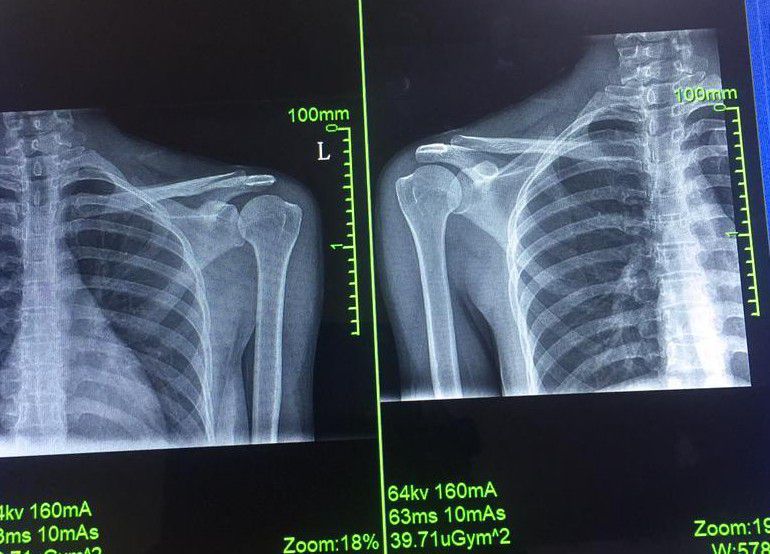

Seniors, this X-ray was taken at my facility. My youngest sister was physically assaulted. A wooden stool was used to hit her left shoulder. She has been complaining of pain for the past few weeks. Prescribers have been unable to figure out what's really going on after the X-ray. Please I would be very glad to welcome your kind views and some possible treatments on the this X-ray. Thanks so you...